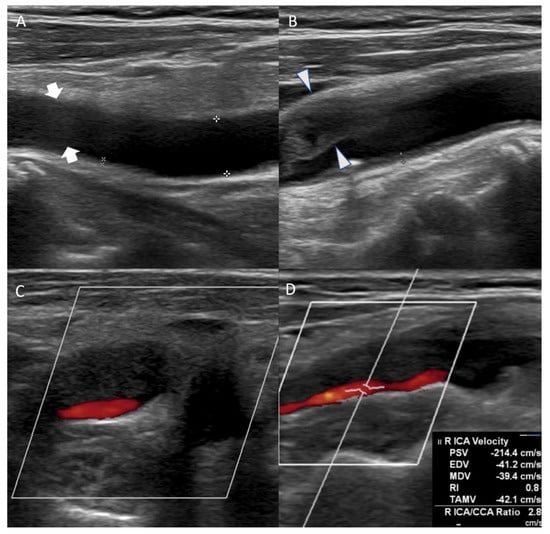

An 86-year-old female patient visited the emergency room complaining of left hemiparesis on waking. This occurred 30 h before her hospital visit. The patient was diagnosed with hypertension 10 years ago and was on medication. She was also diagnosed with hyperlipidemia but refused to take the medication. A neurological examination was performed immediately. The patient exhibited facial palsy, left hemiparesis, and dysarthria. The National Institute of Health Stroke Scale (NIHSS) score was 4, and mental status was alert. Electrocardiography demonstrated atrial fibrillation. The chest radiography revealed cardiomegaly. Brain magnetic resonance (MR) diffusion-weighted imaging (DWI) and fluid-attenuated inversion recovery (FLAIR) detected high-intensity signals suggestive of acute infarction in the right middle cerebral artery (MCA) territory (Figure 1A,B). Severe stenosis of the right internal carotid artery (ICA) was also confirmed on MR angiography (Figure 1C). Laboratory results indicated increased LDL cholesterol (190 mg/dL), total cholesterol (277 mg/dL), and triglyceride (253 mg/dL). Lowered HDL cholesterol (36.4 mg/dL) was also shown in the results. Other laboratory results were normal. The patient was prescribed dual antiplatelet agents (aspirin and clopidogrel) and statin (rosuvastatin 20 mg/day) on admission.

Figure 1.

On brain magnetic resonance diffusion-weighted image (DWI) conducted after admission, infarction in middle cerebral artery territory was confirmed (A). On fluid-attenuated inversion recovery, high-intensity signals in the same area were detected (B). Magnetic resonance angiography (MRA) showed severe stenosis ranging from the right carotid bulb to the right ICA, causing decreased blood flow to the brain ((C), arrow). The overall state of the carotid bulb and ICA was examined through sagittal rotation of MRA (D). Spontaneous regression of former severe stenosis to mild degrees was confirmed on right ICA angiography of digital subtraction angiography on hospitalization day 16 (E).

On the eighth day of hospitalization, the patient complained of dyspnea. Pleural effusion in the right lung was confirmed by follow-up chest X-ray, and the management for pleural effusion was initiated. On the eleventh day of hospitalization, carotid duplex ultrasonography showed extensive stenosis from the right carotid artery bulb to the proximal ICA (Figure 2). Peak systolic velocity (PSV) measured at the site of ICA stenosis was 214.4 cm/s, indicating moderate to severe grade stenosis (Figure 2). Although the patient needed (DSA) and carotid artery stenting to manage the symptomatic CAS, these procedures were delayed to the sixteenth day of hospitalization because of her aggravated general condition due to pleural effusion. On the right ICA angiogram of the DSA, the previously confirmed moderate to severe stenosis had almost regressed. Only mild stenosis with ulcerative plaque was observed (Figure 1D, 15% of the North American Symptomatic Carotid Endarterectomy Trial, NASCET). Therefore, carotid stenting was not performed, and we focused on acute stroke management. There were no additional lesions on the follow-up MRI. The patient was subsequently discharged without significant problems. One month after discharge, the patient’s lipid profile improved and the results are as follows: LDL cholesterol (116 mg/dL), total cholesterol (195 mg/dL), triglyceride (155 mg/dL), and HDL cholesterol (48 mg/dL).